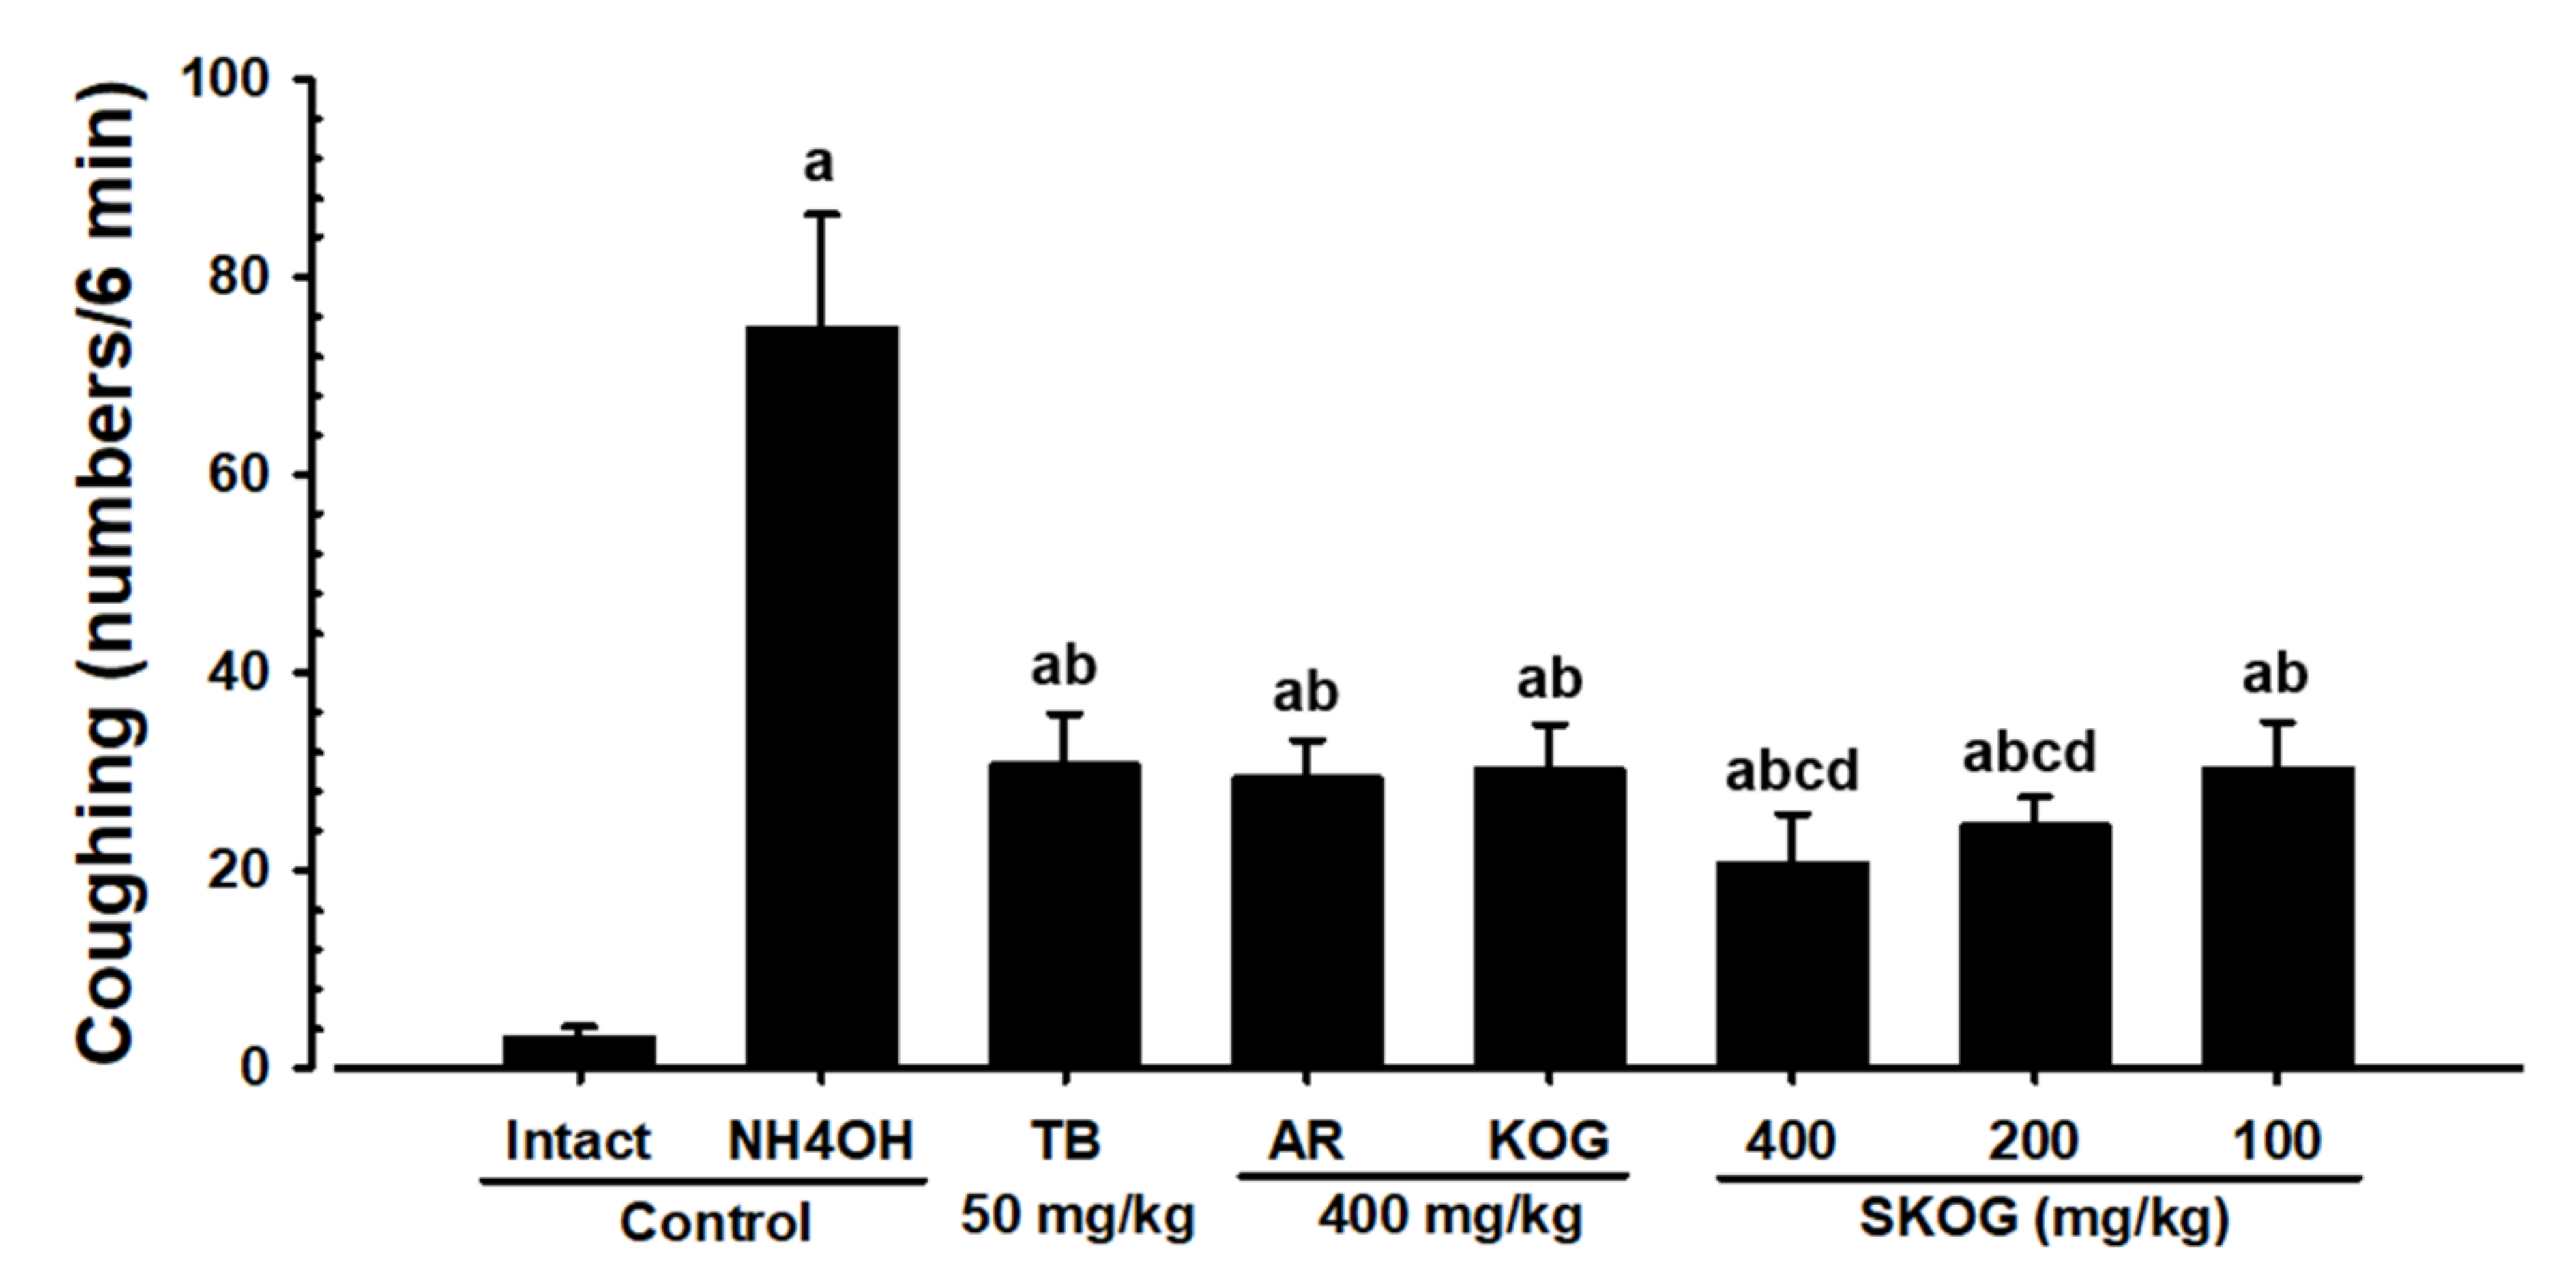

3.2.2. Changes in the Coughing Frequency

3.2.3. Histopathological Findings of the Trachea and Lung